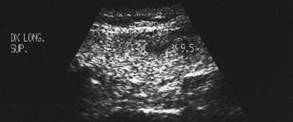

Barbat de 51 ani. Nodul unic in lobul stang, de 25 x 23 x 31mm (9,5 cc), hipoecogen, cu contur net. Citoaspirata: carcinom papilar. Examen histologic: carcinom papilar varianta foliculara

Lob drept, proiectie trasversale si longitudinala.